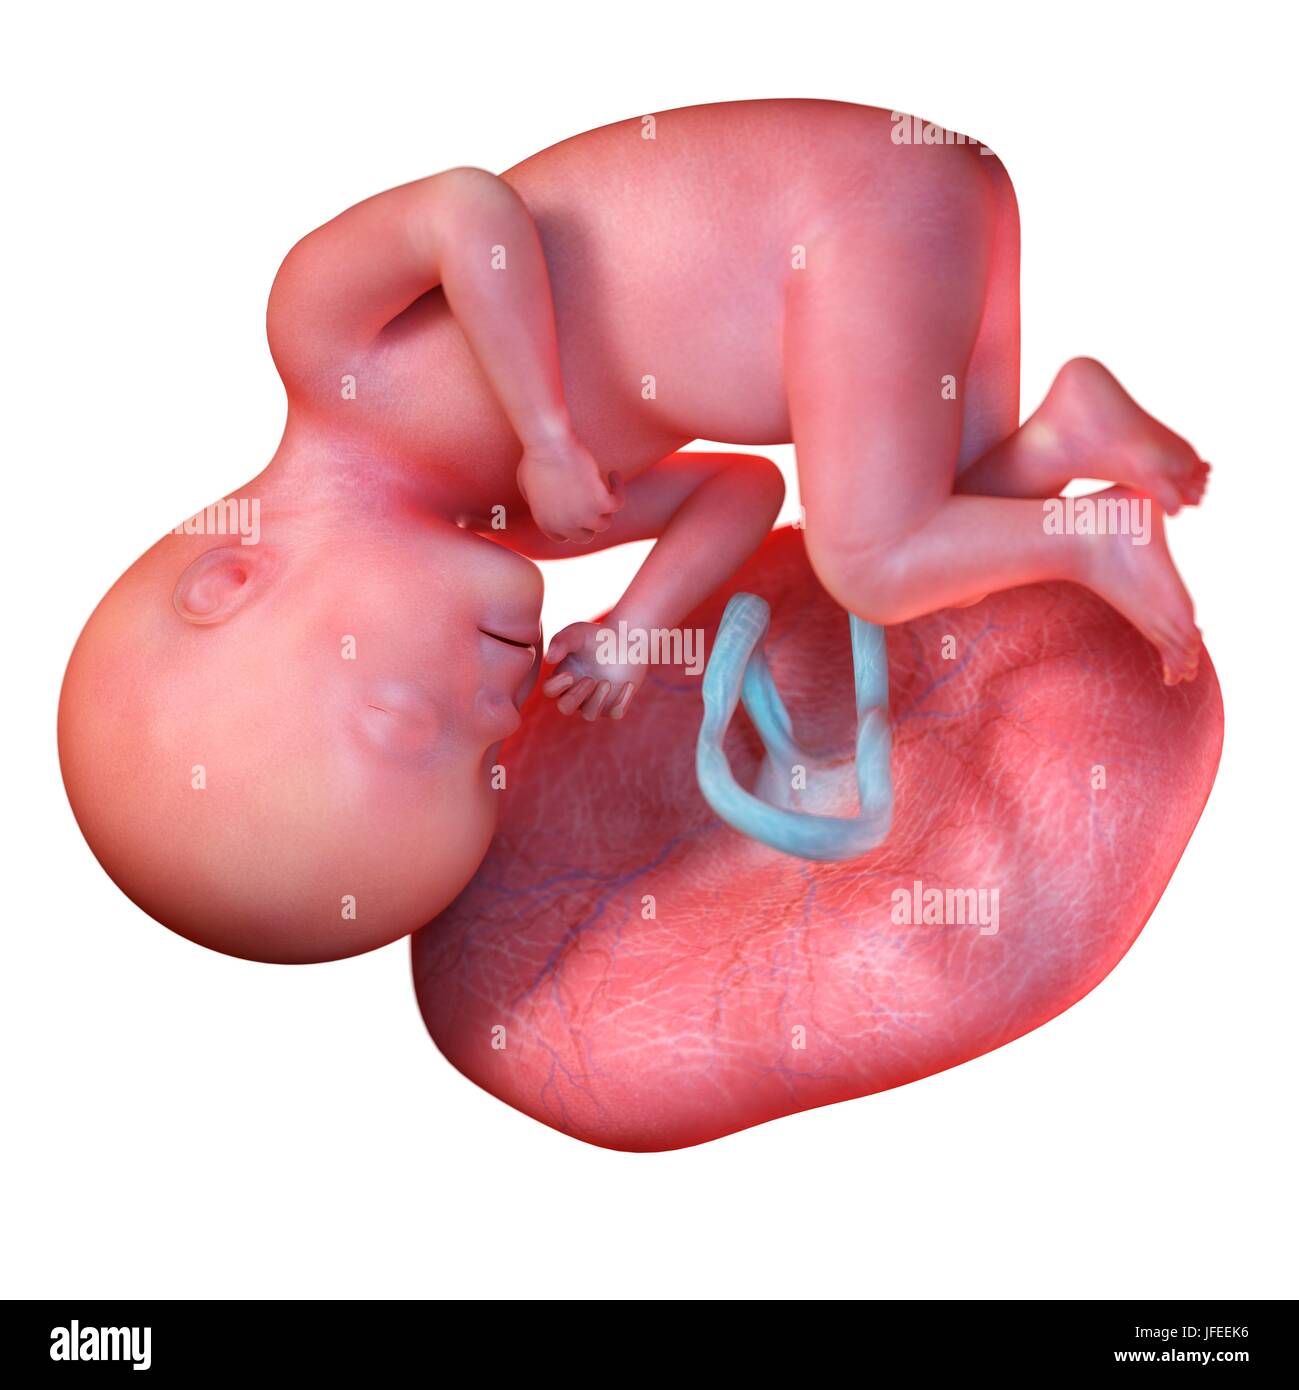

Feto umano età 27 settimane, illustrazione. Foto Stockhttps://www.alamy.it/image-license-details/?v=1https://www.alamy.it/foto-immagine-feto-umano-eta-27-settimane-illustrazione-147221626.html

Feto umano età 27 settimane, illustrazione. Foto Stockhttps://www.alamy.it/image-license-details/?v=1https://www.alamy.it/foto-immagine-feto-umano-eta-27-settimane-illustrazione-147221626.htmlRFJFEEK6–Feto umano età 27 settimane, illustrazione.

Feto umano età 27 settimane, illustrazione. Foto Stockhttps://www.alamy.it/image-license-details/?v=1https://www.alamy.it/foto-immagine-feto-umano-eta-27-settimane-illustrazione-118698396.html

Feto umano età 27 settimane, illustrazione. Foto Stockhttps://www.alamy.it/image-license-details/?v=1https://www.alamy.it/foto-immagine-feto-umano-eta-27-settimane-illustrazione-118698396.htmlRFGW350C–Feto umano età 27 settimane, illustrazione.

Feto umano età 27 settimane, illustrazione. Foto Stockhttps://www.alamy.it/image-license-details/?v=1https://www.alamy.it/foto-immagine-feto-umano-eta-27-settimane-illustrazione-112681659.html

Feto umano età 27 settimane, illustrazione. Foto Stockhttps://www.alamy.it/image-license-details/?v=1https://www.alamy.it/foto-immagine-feto-umano-eta-27-settimane-illustrazione-112681659.htmlRFGF92GY–Feto umano età 27 settimane, illustrazione.

Feto umano età 27 settimane, illustrazione. Foto Stockhttps://www.alamy.it/image-license-details/?v=1https://www.alamy.it/foto-immagine-feto-umano-eta-27-settimane-illustrazione-111973828.html

Feto umano età 27 settimane, illustrazione. Foto Stockhttps://www.alamy.it/image-license-details/?v=1https://www.alamy.it/foto-immagine-feto-umano-eta-27-settimane-illustrazione-111973828.htmlRFGE4RN8–Feto umano età 27 settimane, illustrazione.

Feto umano alla settimana 27, illustrazione Foto Stockhttps://www.alamy.it/image-license-details/?v=1https://www.alamy.it/feto-umano-alla-settimana-27-illustrazione-image463765768.html

Feto umano alla settimana 27, illustrazione Foto Stockhttps://www.alamy.it/image-license-details/?v=1https://www.alamy.it/feto-umano-alla-settimana-27-illustrazione-image463765768.htmlRF2HXE9Y4–Feto umano alla settimana 27, illustrazione

Feto umano alla settimana 27, illustrazione Foto Stockhttps://www.alamy.it/image-license-details/?v=1https://www.alamy.it/feto-umano-alla-settimana-27-illustrazione-image463765769.html

Feto umano alla settimana 27, illustrazione Foto Stockhttps://www.alamy.it/image-license-details/?v=1https://www.alamy.it/feto-umano-alla-settimana-27-illustrazione-image463765769.htmlRF2HXE9Y5–Feto umano alla settimana 27, illustrazione

Feto umano alla settimana 27, illustrazione Foto Stockhttps://www.alamy.it/image-license-details/?v=1https://www.alamy.it/feto-umano-alla-settimana-27-illustrazione-image463765837.html

Feto umano alla settimana 27, illustrazione Foto Stockhttps://www.alamy.it/image-license-details/?v=1https://www.alamy.it/feto-umano-alla-settimana-27-illustrazione-image463765837.htmlRF2HXEA1H–Feto umano alla settimana 27, illustrazione

Feto umano alla settimana 27, illustrazione Foto Stockhttps://www.alamy.it/image-license-details/?v=1https://www.alamy.it/feto-umano-alla-settimana-27-illustrazione-image463765857.html

Feto umano alla settimana 27, illustrazione Foto Stockhttps://www.alamy.it/image-license-details/?v=1https://www.alamy.it/feto-umano-alla-settimana-27-illustrazione-image463765857.htmlRF2HXEA29–Feto umano alla settimana 27, illustrazione

Feto umano alla settimana 27, illustrazione Foto Stockhttps://www.alamy.it/image-license-details/?v=1https://www.alamy.it/feto-umano-alla-settimana-27-illustrazione-image463765740.html

Feto umano alla settimana 27, illustrazione Foto Stockhttps://www.alamy.it/image-license-details/?v=1https://www.alamy.it/feto-umano-alla-settimana-27-illustrazione-image463765740.htmlRF2HXE9X4–Feto umano alla settimana 27, illustrazione

Anatomia del feto umano alla settimana 27, illustrazione Foto Stockhttps://www.alamy.it/image-license-details/?v=1https://www.alamy.it/anatomia-del-feto-umano-alla-settimana-27-illustrazione-image463765847.html

Anatomia del feto umano alla settimana 27, illustrazione Foto Stockhttps://www.alamy.it/image-license-details/?v=1https://www.alamy.it/anatomia-del-feto-umano-alla-settimana-27-illustrazione-image463765847.htmlRF2HXEA1Y–Anatomia del feto umano alla settimana 27, illustrazione

Anatomia del feto umano alla settimana 27, illustrazione Foto Stockhttps://www.alamy.it/image-license-details/?v=1https://www.alamy.it/anatomia-del-feto-umano-alla-settimana-27-illustrazione-image463765833.html

Anatomia del feto umano alla settimana 27, illustrazione Foto Stockhttps://www.alamy.it/image-license-details/?v=1https://www.alamy.it/anatomia-del-feto-umano-alla-settimana-27-illustrazione-image463765833.htmlRF2HXEA1D–Anatomia del feto umano alla settimana 27, illustrazione

Anatomia del feto umano alla settimana 27, illustrazione Foto Stockhttps://www.alamy.it/image-license-details/?v=1https://www.alamy.it/anatomia-del-feto-umano-alla-settimana-27-illustrazione-image463765820.html

Anatomia del feto umano alla settimana 27, illustrazione Foto Stockhttps://www.alamy.it/image-license-details/?v=1https://www.alamy.it/anatomia-del-feto-umano-alla-settimana-27-illustrazione-image463765820.htmlRF2HXEA10–Anatomia del feto umano alla settimana 27, illustrazione

Anatomia del feto umano alla settimana 27, illustrazione Foto Stockhttps://www.alamy.it/image-license-details/?v=1https://www.alamy.it/anatomia-del-feto-umano-alla-settimana-27-illustrazione-image463765855.html

Anatomia del feto umano alla settimana 27, illustrazione Foto Stockhttps://www.alamy.it/image-license-details/?v=1https://www.alamy.it/anatomia-del-feto-umano-alla-settimana-27-illustrazione-image463765855.htmlRF2HXEA27–Anatomia del feto umano alla settimana 27, illustrazione

Anatomia del feto umano alla settimana 27, illustrazione Foto Stockhttps://www.alamy.it/image-license-details/?v=1https://www.alamy.it/anatomia-del-feto-umano-alla-settimana-27-illustrazione-image463765763.html

Anatomia del feto umano alla settimana 27, illustrazione Foto Stockhttps://www.alamy.it/image-license-details/?v=1https://www.alamy.it/anatomia-del-feto-umano-alla-settimana-27-illustrazione-image463765763.htmlRF2HXE9XY–Anatomia del feto umano alla settimana 27, illustrazione